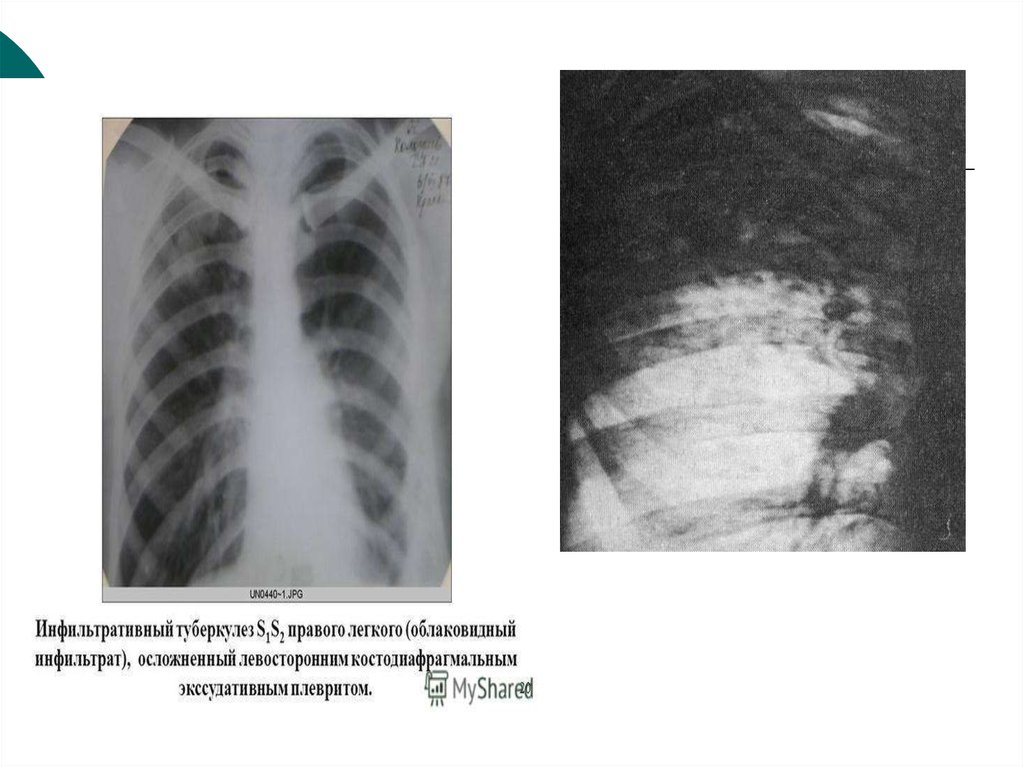

Иллюстрации по теме очагового и инфильтративного туберкулеза